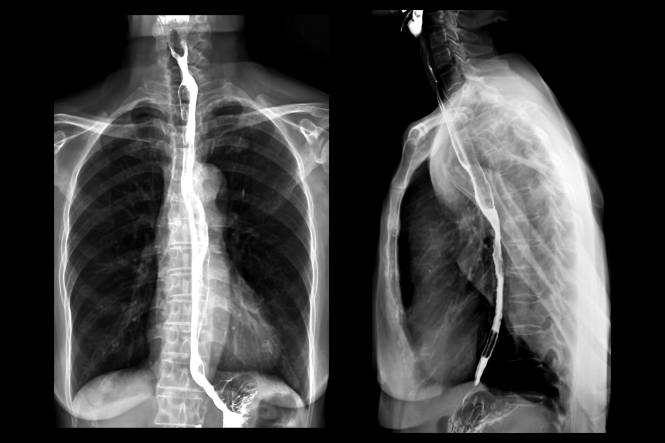

Digestive system – tests and procedures

A range of tests and procedures are used to check on your digestive health and to diagnose and monitor any digestive system condition you may have. Find out about these tests and procedures here.